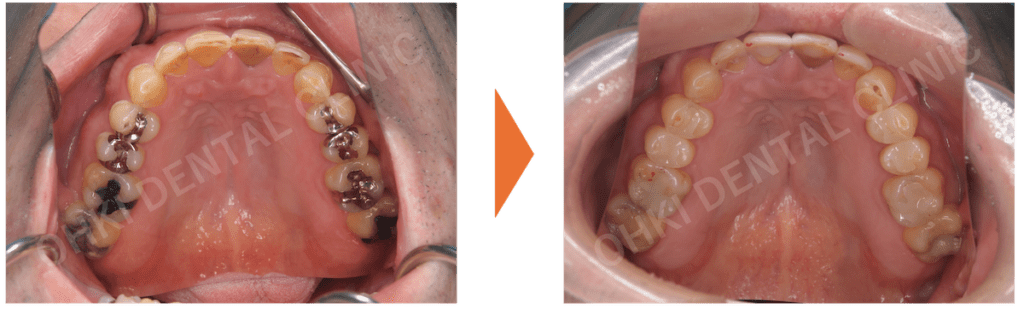

・主訴である右下7番は、コアごと脱離しており、歯根破折を認めました。

・パノラマレントゲン写真では、左下6番にも歯折と周辺の骨吸収が認められました。

・全体的にカリエス(虫歯)が多く、非常にカリエスリスクが高い状態でした。

抜歯、その他の歯の虫歯治療、TBI(歯磨き指導)、スケーリングなどのOH(口腔衛生)レベルの改善をしっかりと行いました。 - 抜歯と治癒期間:

抜歯後、骨・軟組織の治癒を待つため、約3ヶ月間の待機期間がありました。 - インプラント埋入:

GBR(骨再生誘導法)を含めたインプラント埋入処置を実施しました。 - 上部構造の装着(ファイナルセット):

インプラント体に最終的なセラミック素材の上部構造をセットしました。

歯根破折により周辺に骨吸収が起こっていたため、骨の不足を補うためのGBRも含めて、インプラント治療を実施しました。